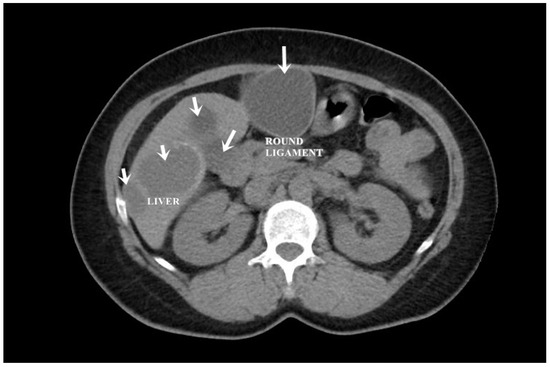

A CT examination revealed multiple cystic images in the hepatic segments V, VI, and VII, with subhepatic extension and involvement at the fissures of the venous ligament. Cystic images were also observed in the anterior abdominal wall and submesocolic (Figure 5, Figure 6, Figure 7, Figure 8 and Figure 9). Blood tests showed no significant abnormalities, and ELISA determination of IgG class antibodies to Echinococcus granulosus was positive at 1.66 IV (with values considered negative at ≤0.9 IV and positive at ≥1.1 IV).

The imaging highlights hepatic cysts in segments V, VI, and VII, a large cystic formation in the round ligament, a cyst in the parietal peritoneum, two cysts in the greater omentum, and two cysts located in the submesocolic enteral mesentery.

Figure 3. Liver and round ligament hydatid cysts (indicated by arrows).